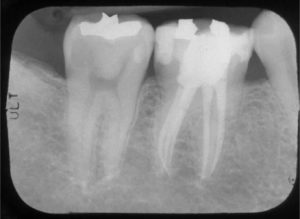

The length of the root canal is determined and the infected pulp is removed.

At the same visit, the canal where the nerve is located will be reshaped and prepared to accept a special root canal filling material.

The final step in your root canal will be the sealing of the root canal with a sterile, plastic material called gutta percha. This is done in order to prevent possible future infection.